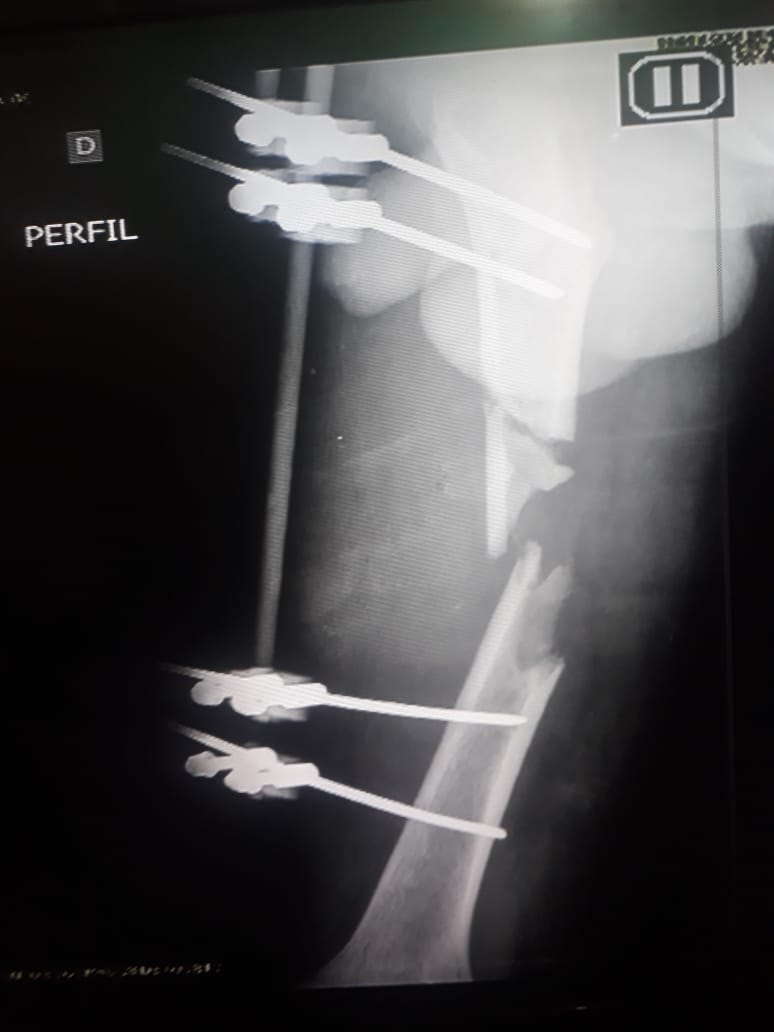

O acidente deixou fraturas no braço e no fêmur de Filipe. Apesar da sorte de ter sobrevivido sem maiores problemas, Filipe ainda não pode seguir a vida tranquilamente, pois o acidente o fez perder 7 centímetros de perna, e há um ano e 7 meses, ele aguarda por uma cirurgia no Hospital Adriano Jorge, que a todo esse tempo, alega falta de material.